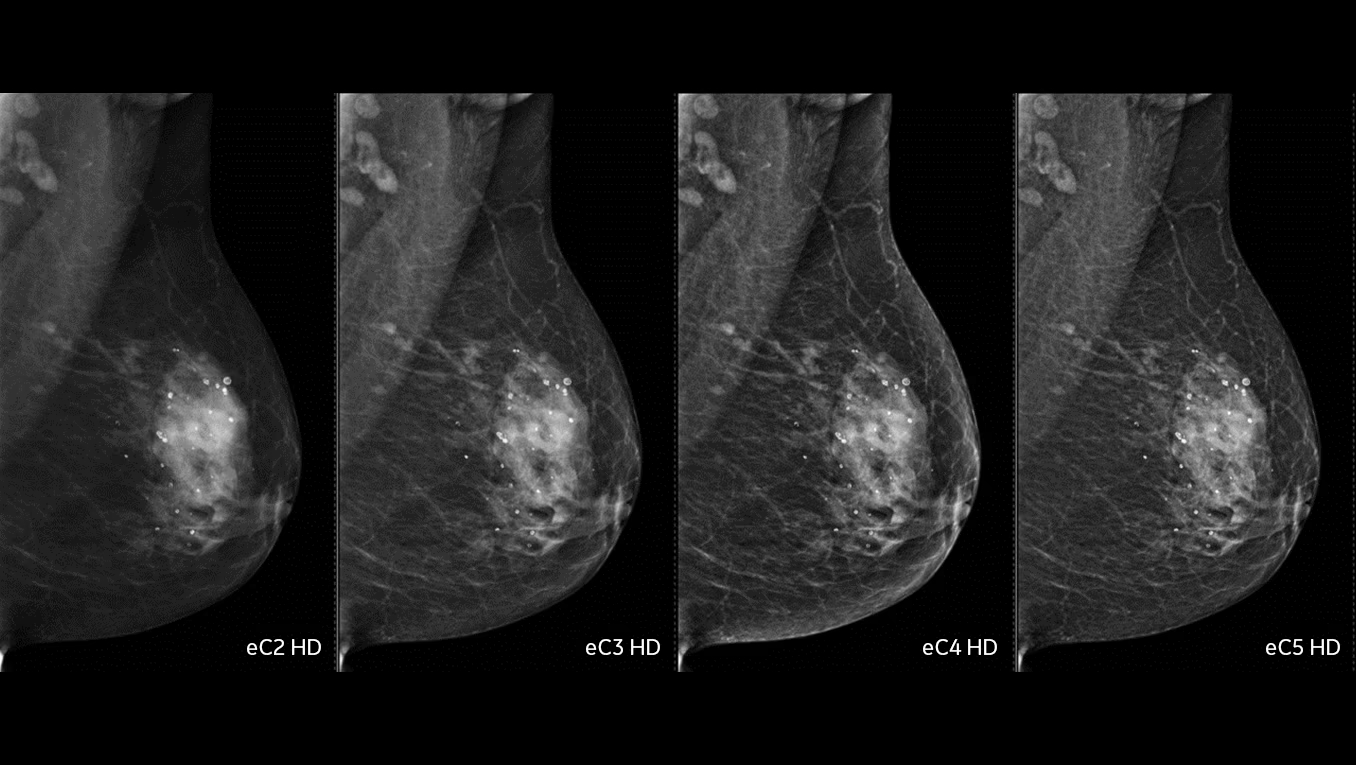

Quattro livelli di contrasto permettono una lettura più accurata delle immagini, migliorando la capacità diagnostica e riducendo il rischio di interpretazioni incomplete.